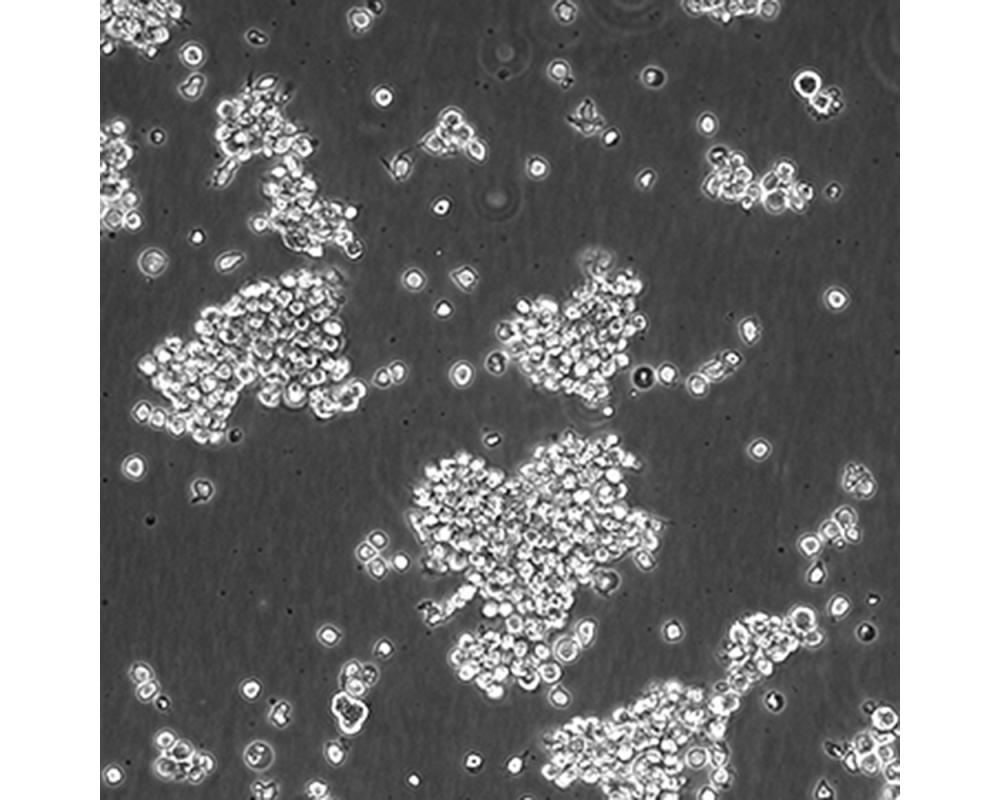

產品名稱 SU-DHL-2

中文名稱 人間變性大細胞淋巴瘤細胞

組織來源 間變性大細胞淋巴瘤;胸腔積液轉移;女性

生長特性 懸浮

培養基 1640,90%;FBS,10%;雙抗。

傳代方法 Maintain cultures at a cell concentraion between between 1 X 10(5) and 1 X 10(6) viable cells/ml.

培養條件 Atmosphere: Air, 95%; CO2, 5%。Temperature: 37℃